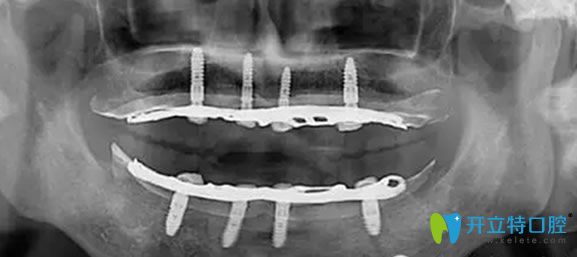

全口數(shù)字化X光影像

老媽的牙齒,可能因?yàn)樯盍?xí)慣的原因,導(dǎo)致牙齒脫落嚴(yán)重,按了活動假牙,當(dāng)時對于口腔牙齒也不是很了解,覺著活動假牙價格合適。按上之后,感覺強(qiáng)度不是太好,吃東西容易塞牙,造成目前,牙齦有點(diǎn)萎縮。來院經(jīng)過王杰院長檢查后,需要對牙齦萎縮進(jìn)行治療,炎癥得到控制后在再進(jìn)行種植牙修復(fù)。

經(jīng)過一個月的漫長等待,老媽終于做了種植牙,當(dāng)場就拿蘋果做實(shí)驗(yàn),感覺種出來的牙齒和真牙一樣舒服。老媽再次擁有滿口舒適的好牙,恢復(fù)了咀嚼功能,真心覺得很不錯,感覺醫(yī)生技術(shù)水平也很專業(yè),很細(xì)心,走的時候還給我們囑咐種植牙的術(shù)后護(hù)理方法。